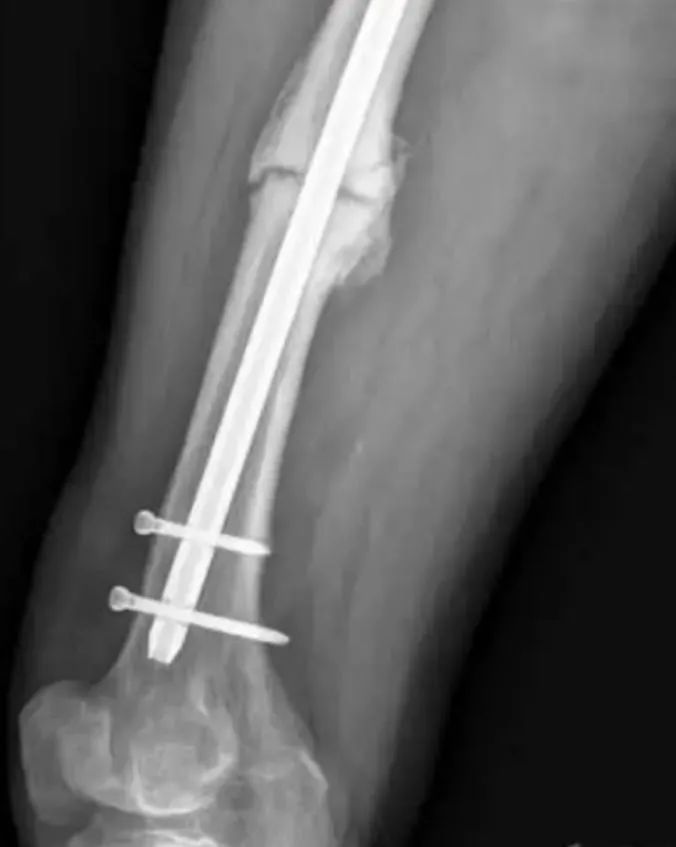

Souvent, le clou intramédullaire peut devoir être retiré avant qu'une pseudarthrose nécessite une chirurgie de révision.Cependant, une fois la fracture cicatrisée, le retrait du clou centromédullaire est devenu controversé.Une douleur persistante ou progressive après la guérison de la fracture peut être une indication pour le retrait de l'ongle.Bien sûr, le retrait aveugle de la fixation interne peut ne pas résoudre ou même aggraver le problème tant que la cause de la douleur n'est pas identifiée.Le chirurgien doit soigneusement tenir compte de la présence des indications suivantes lorsqu'il décide de retirer ou non le clou intramédullaire.

Retirer un clou intramédullaire cassé est un défi.Les échecs de fixation interne sont généralement des échecs de fatigue dus à des charges répétées sous le seuil.Au cours du processus de cicatrisation secondaire de la formation du cal, le clou intramédullaire est stimulé par des forces de déformation répétées.Par rapport aux anciens clous intramédullaires fendus, les nouveaux clous intramédullaires fermés à section transversale sont plus résistants à de telles forces de déformation.De même, une augmentation de diamètre peut améliorer les propriétés anti-fatigue du clou centromédullaire.Une fois que le clou intramédullaire est cassé, cela indique qu'il y a encore du mouvement à l'extrémité de la fracture, de sorte que la fracture du clou intramédullaire peut être considérée comme l'un des signes de pseudarthrose ;dans ce cas, il est nécessaire de retirer le clou intramédullaire pour un traitement ultérieur.

Une fois le diagnostic de pseudarthrose établi, l'ablation du clou centromédullaire doit être envisagée avant qu'il ne se rompe.Déterminer quand un clou intramédullaire se rompt est souvent difficile, alors quand retirer le clou intramédullaire est controversé.Cependant, le retrait d'un clou intramédullaire intact est beaucoup plus simple que le retrait d'un clou intramédullaire cassé, de sorte que le chirurgien doit tenir compte de ce facteur dans les options de traitement ultérieures.